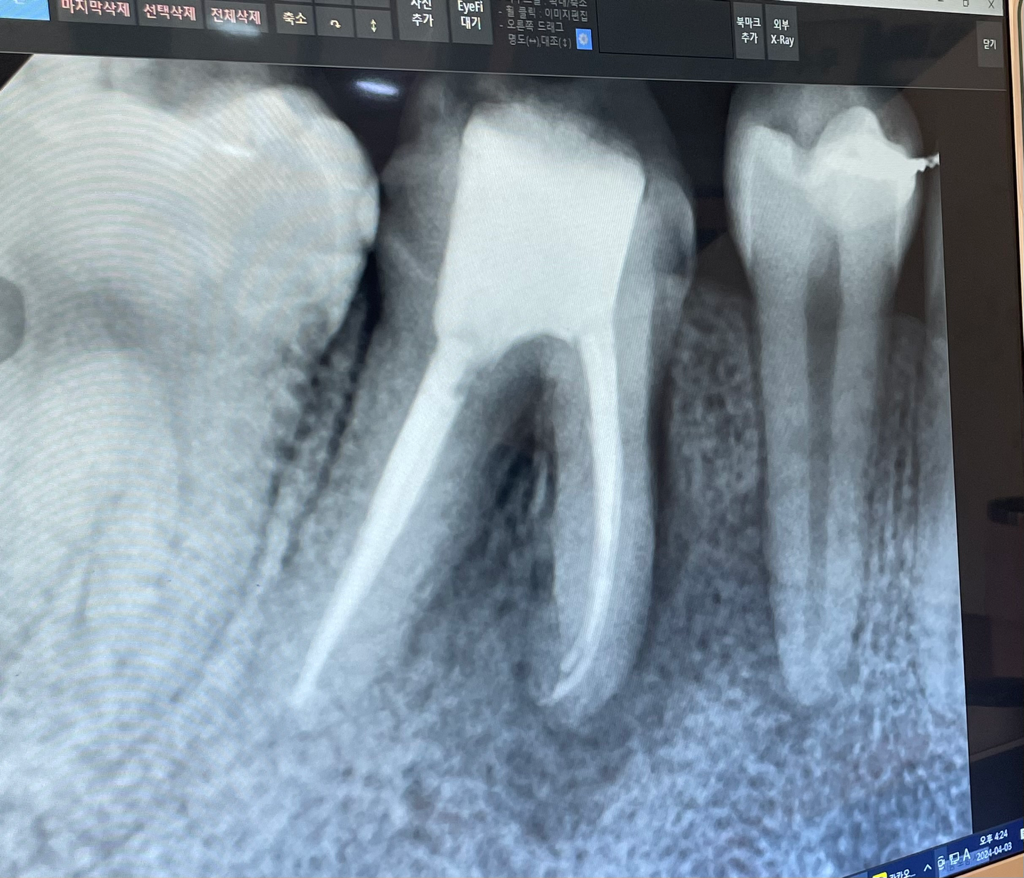

이미 염증으로 인해 뿌리랑 뼈까지 다 녹은 상태이다. 심지어 옆에 치아 신경까지 염증이 옮겨가고 있어서 살리기 불가 발치하고 임플란트 해야함.

(교정 진행했던 치과이기에 자료가 있었으며 교정과 아닌 일반과 가서 검사 받음) 교정 진행할 때 찍었던 엑스레이 사진을 보니 그때는 누가 신경치료 한건지 궁금할 정도로 잘되어 있었다. 근데 (1년 반~2년 사이)염증이 많이 생긴걸 보아하니 두가지 원인인데

두번째는 해당 치아 신경이 살짝 꺾여있어서 끝쪽에 세균이 남 아있었고 그래서 그 세균이 번져 염증이 생긴 것.

치과 의사 선생님께서는 전자의 가능성도 있지만 후자의 가능성이 더 크다고 판단하시고 재신경치료 진행해보고 실패시 임플란트 진행하자고 하셨습니다.

또한 A치과와는 달리 옆치아 신경이 아직은 위험하지 않다고 하셨습니다.

사진상으로는 염증이 뼈로 퍼져서 잇몸뼈가 많이 녹아 있습니다. 전후 사진이 없어 상황이 개선되고 있는지 나빠지는지 파악은 힘드나 이 상태에서는 재신경치료보다는 치근단 절제술이 적절할 수도 있습니다.

엑스레이 상으로 보면 잇몸 뼈가 많이 녹은건 사실입니다. 둘다 치료 방법이긴 합니다. 하지만 환자분이 치아를 살려 보고 싶다면 재신경치료를 한번 해볼순 잇지만 발치를 해야될 가능성이 높아 보이긴합니다.